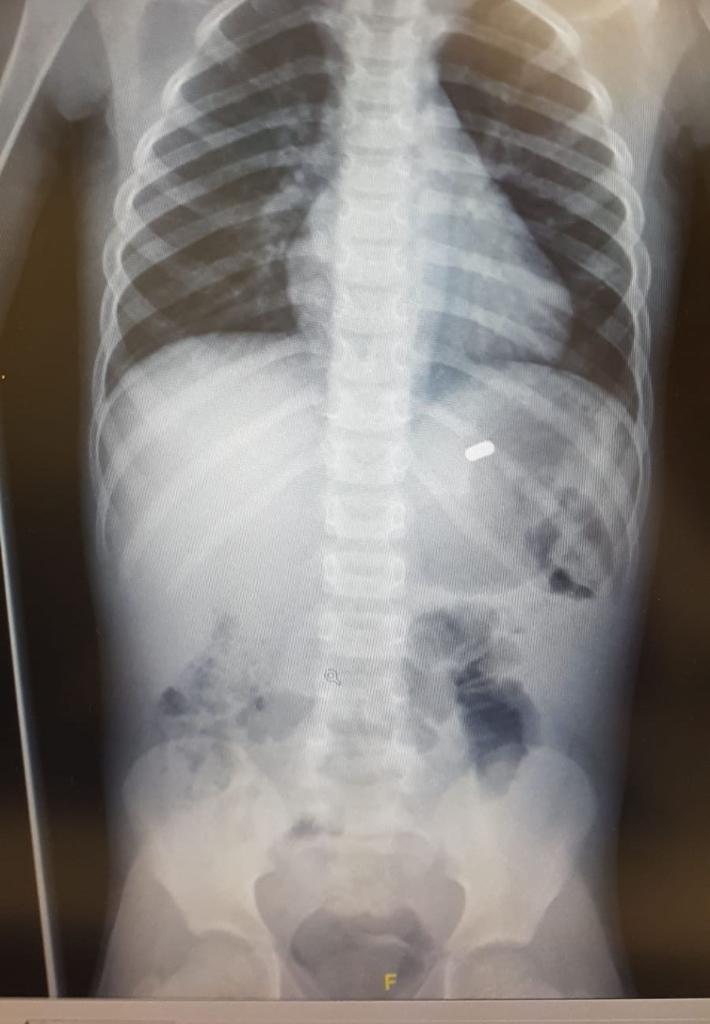

בצילום הדמיה שנערך לילד נחשף גוף זר בחלל הקיבה. הילד הובהל לחדר ניתוח ושם ביצע ד"ר שלומי כהן, מנהל יחידת הגסטרו ילדים, גסטרוסקופיה בהרדמה כללית, במהלכו הוחדר צינור דרך הפה לאורך מערכת העיכול.

בקיבה נצפו 4 מגנטים דבוקים אחד לשני ודבוקים לקפל קיבה גדול. באמצעות מכשור מיוחד נשלפו המגנטים בזהירות רבה על מנת שלא ייפרדו אחד מהשני. לאחר הוצאת המגנטים מהקיבה, ניתן היה לראות בקיבה כי המגנטים גרמו לכיב ודלקת מקומית אשר היא גרמה לכאבי הבטן וההקאות.